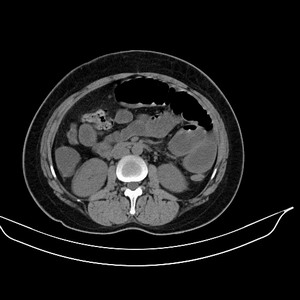

女 42岁 子宫肌瘤于外院术后两天,感腹胀。x线提示肠梗阻。

子宫肌瘤于外院术后两天,出现肠扭转梗阻,很明显。但右下腹部出现的线状高密度,是什么呢?有什么手术会有这样的物品呢?不会把电刀的导线遗留在腹腔吧!?

结果:术后纱布遗留,术后麻痹性肠梗阻肠梗阻

上面的图像是我们从手术室拿来的纱布做了个ct平扫,发现纱布里确实存在有一条致密影。后得知致密影是为防止手术时纱布遗留而设计。关腹时怀疑纱布遗留可做个床边透视或拍片可明确。